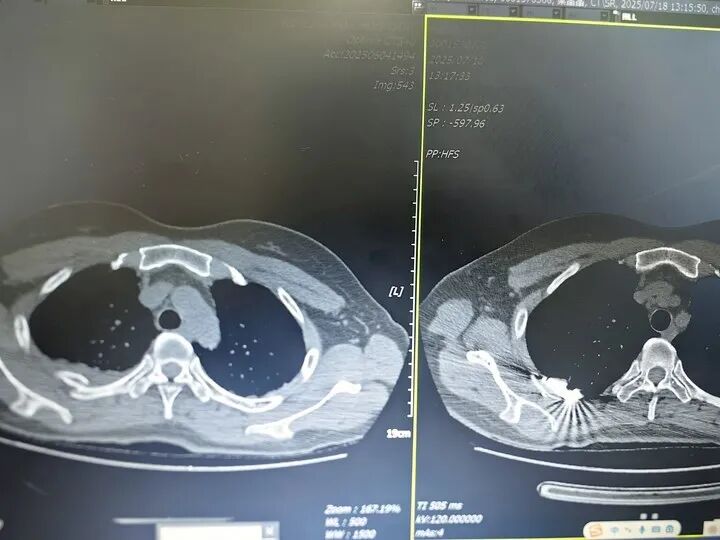

患者因外伤导致多根肋骨骨折,其中部分肋骨断端移位明显,合并胸腔内少量积液,病情复杂。若单纯采用胸腔镜微创手术,对于靠近胸骨、肩胛骨等特殊部位的骨折,操作空间受限,固定难度较大;若完全采用传统开放手术,又会造成较大创伤,不利于术后恢复。